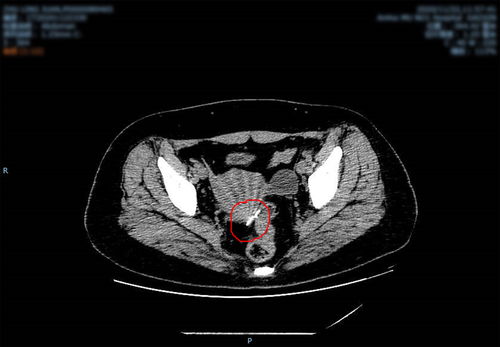

肾癌-无痛血尿一次,一年后腰痛查出肾癌

在泌尿系统肿瘤的谱系中,肾癌常被称为“沉默的杀手”。其早期阶段,肿瘤深藏于腹膜后,肾脏本身强大的代偿能力与内部缺乏痛觉神经的特性,使得它能够在悄无声息中生长壮大。许多患者首次察觉异常,往往并非因为肾脏本身的直接不适,而是源于一些看似无关或间歇性出现的全身性信号。其中, 无痛性肉眼血尿 是最具代表性,却也最易被误解和忽略的早期征兆之一。本文将通过一个典型的临床...